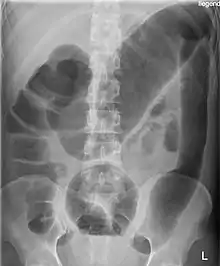

Toxic megacolon is an acute form of colonic distension.[2] It is characterized by a very dilated colon (megacolon), accompanied by abdominal distension (bloating), and sometimes fever, abdominal pain, or shock.

There may be signs of septic shock. A physical examination reveals abdominal tenderness and possible loss of bowel sounds. An abdominal radiography shows colonic dilation. White blood cell count is usually elevated. Severe sepsis may present with hypothermia or leukopenia.

Massively dilated colon with air-fluid level can be seen on abdominal radiograph or CT scan.[5][6]